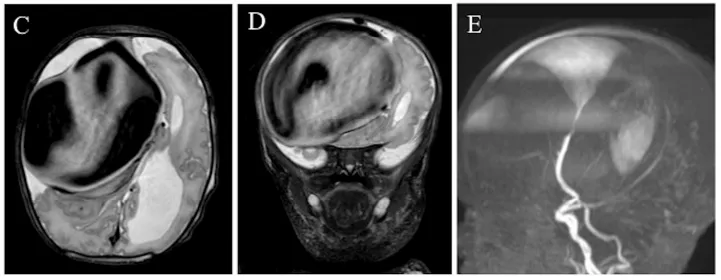

由于亨利临床状态稳定,医学团队决定在亨利出生后第8天行数字减影血管造影(DSA),以完成病变的血管内栓塞治疗。术后即刻造影显示主瘘道完全闭塞(图2C)。

图2C

术后第1天,亨利神经状态轻度恶化。急诊CT示瘤囊内血栓进展、囊腔较前增大;CTA发现右侧大脑中动脉(MCA)远端一新发粗大供血支参与瘘口(图3A),该支在术前DSA中并未显影。

图3A